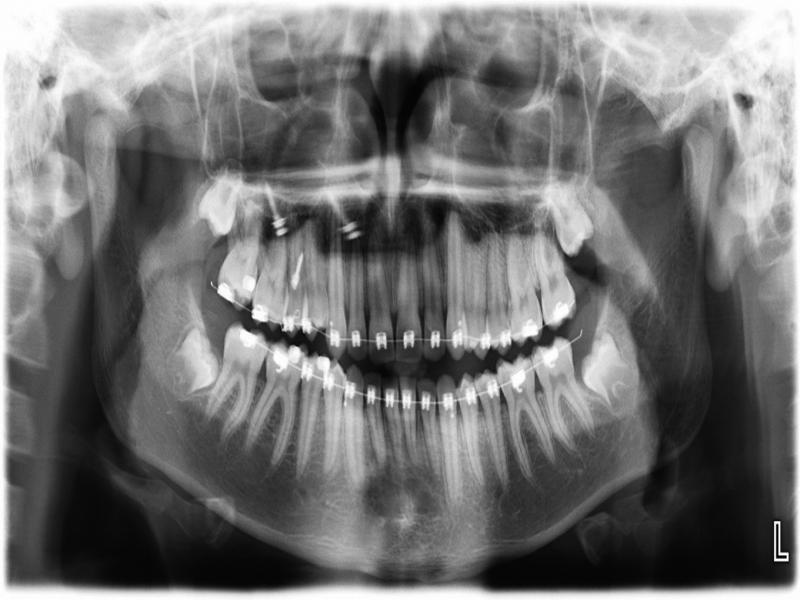

Figure 4.